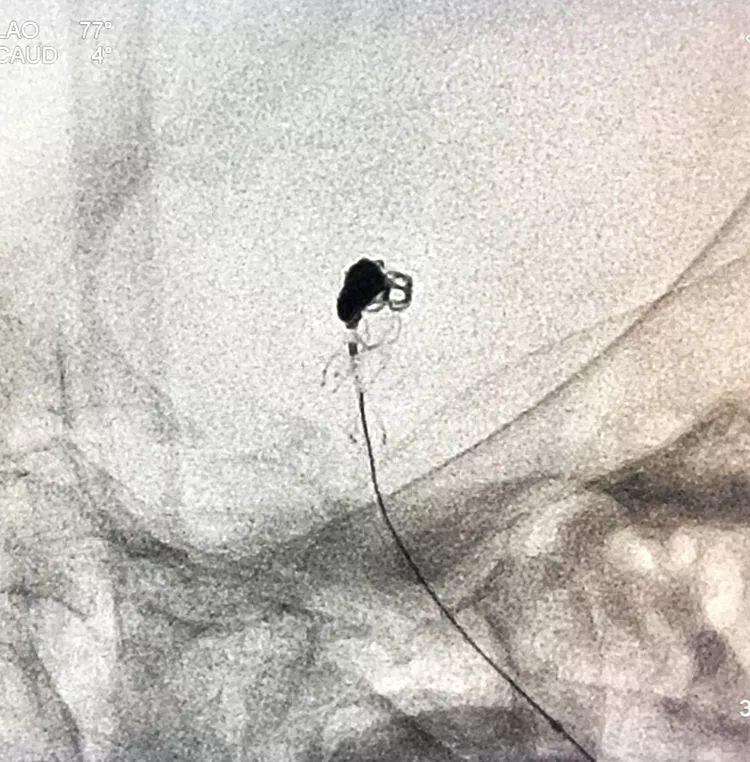

换用一根新的Echelon10微导管,头端塑成C型,以Arvigo14微导丝引导(先前的Sychro14微导丝的头端已经有损了),经LVIS支架内部接近瘤腔后部的死腔,但微导丝可以进入死腔,微导管头死活钻不进去,被LVIS支架的网丝挡住去路,怎么办?那就隔着渔网袜挠痒!

微导管头顶在支架网眼处,投送一枚1.5-2的小圈,一开始弹簧圈走行入载瘤动脉(支架)内,用扭具调整弹簧圈头端的行进方向,并随之微调微导管头的方向和张力,圈终于成功钻入死腔!

再投入一枚1.5-3的小圈

继续钻入一枚1.5-2的小圈

嗯,完美收官!

回到工作位造影,显示基底动脉顶端动脉瘤完全栓塞,基底动脉顶端四根血管畅通。